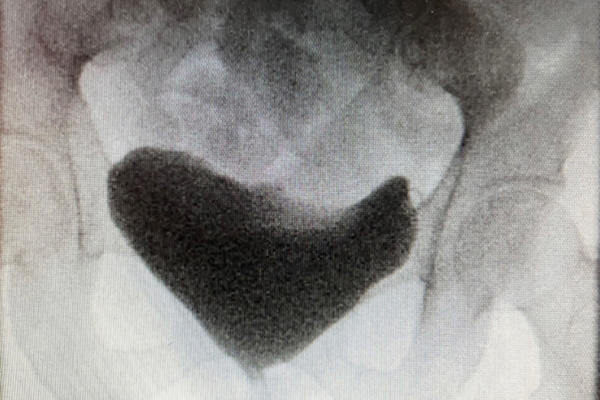

Cystoplasty

Functional and reconstructive urology

Upper tract abnormalities

The role of embolisation in urology

Benign upper tract abnormalities